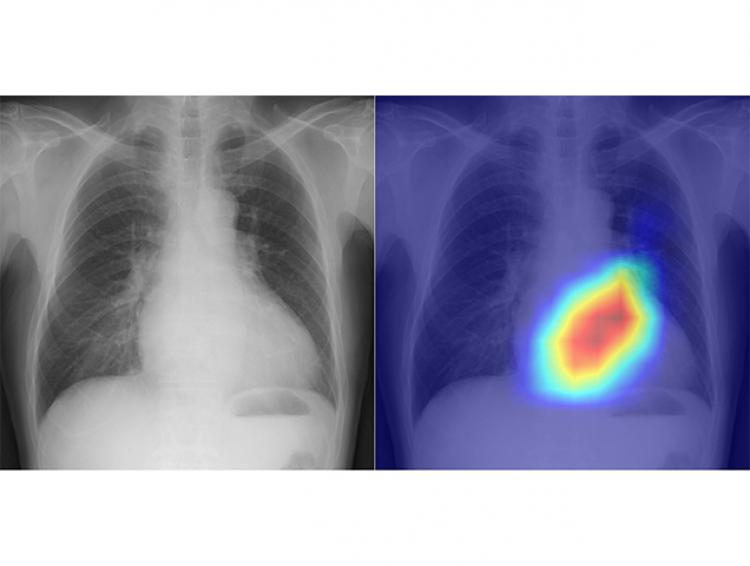

AI detects fatty liver disease with chest X-rays